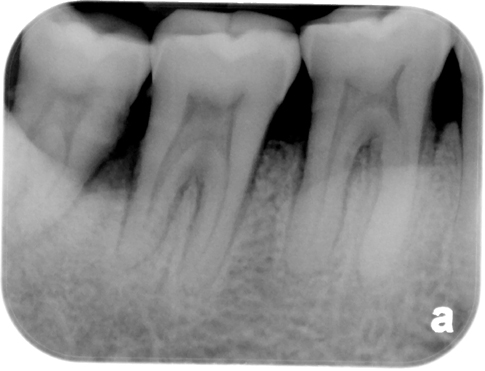

Interne resorptie

Apicale wortelresorptie

Externe resorptie

Pulpasclerose

Pulpolieten

Hypercementose